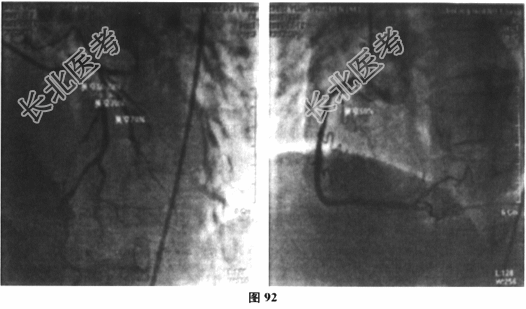

- 多项选择题3.[提示]患者入院后予以急诊冠脉介入治疗,术中见冠脉分布呈右优势型, LM末端狭窄10%~20%,LAD近中段狭窄30%, D1段狭窄70%,LCX近段完全闭塞, 管腔内可见血栓影,RCA近中段长病变大于20mm, 狭窄最重处约50%(图92、图93),予以p-LCX植入支架2枚, 术后患者胸闷症状缓解,但术后患者间断低热, 体温最高38.2℃,伴右侧颞部搏动性痛伴头胀, 余无其他不适,监测血沉85mm/1小时末, CRP38.3mg/L。